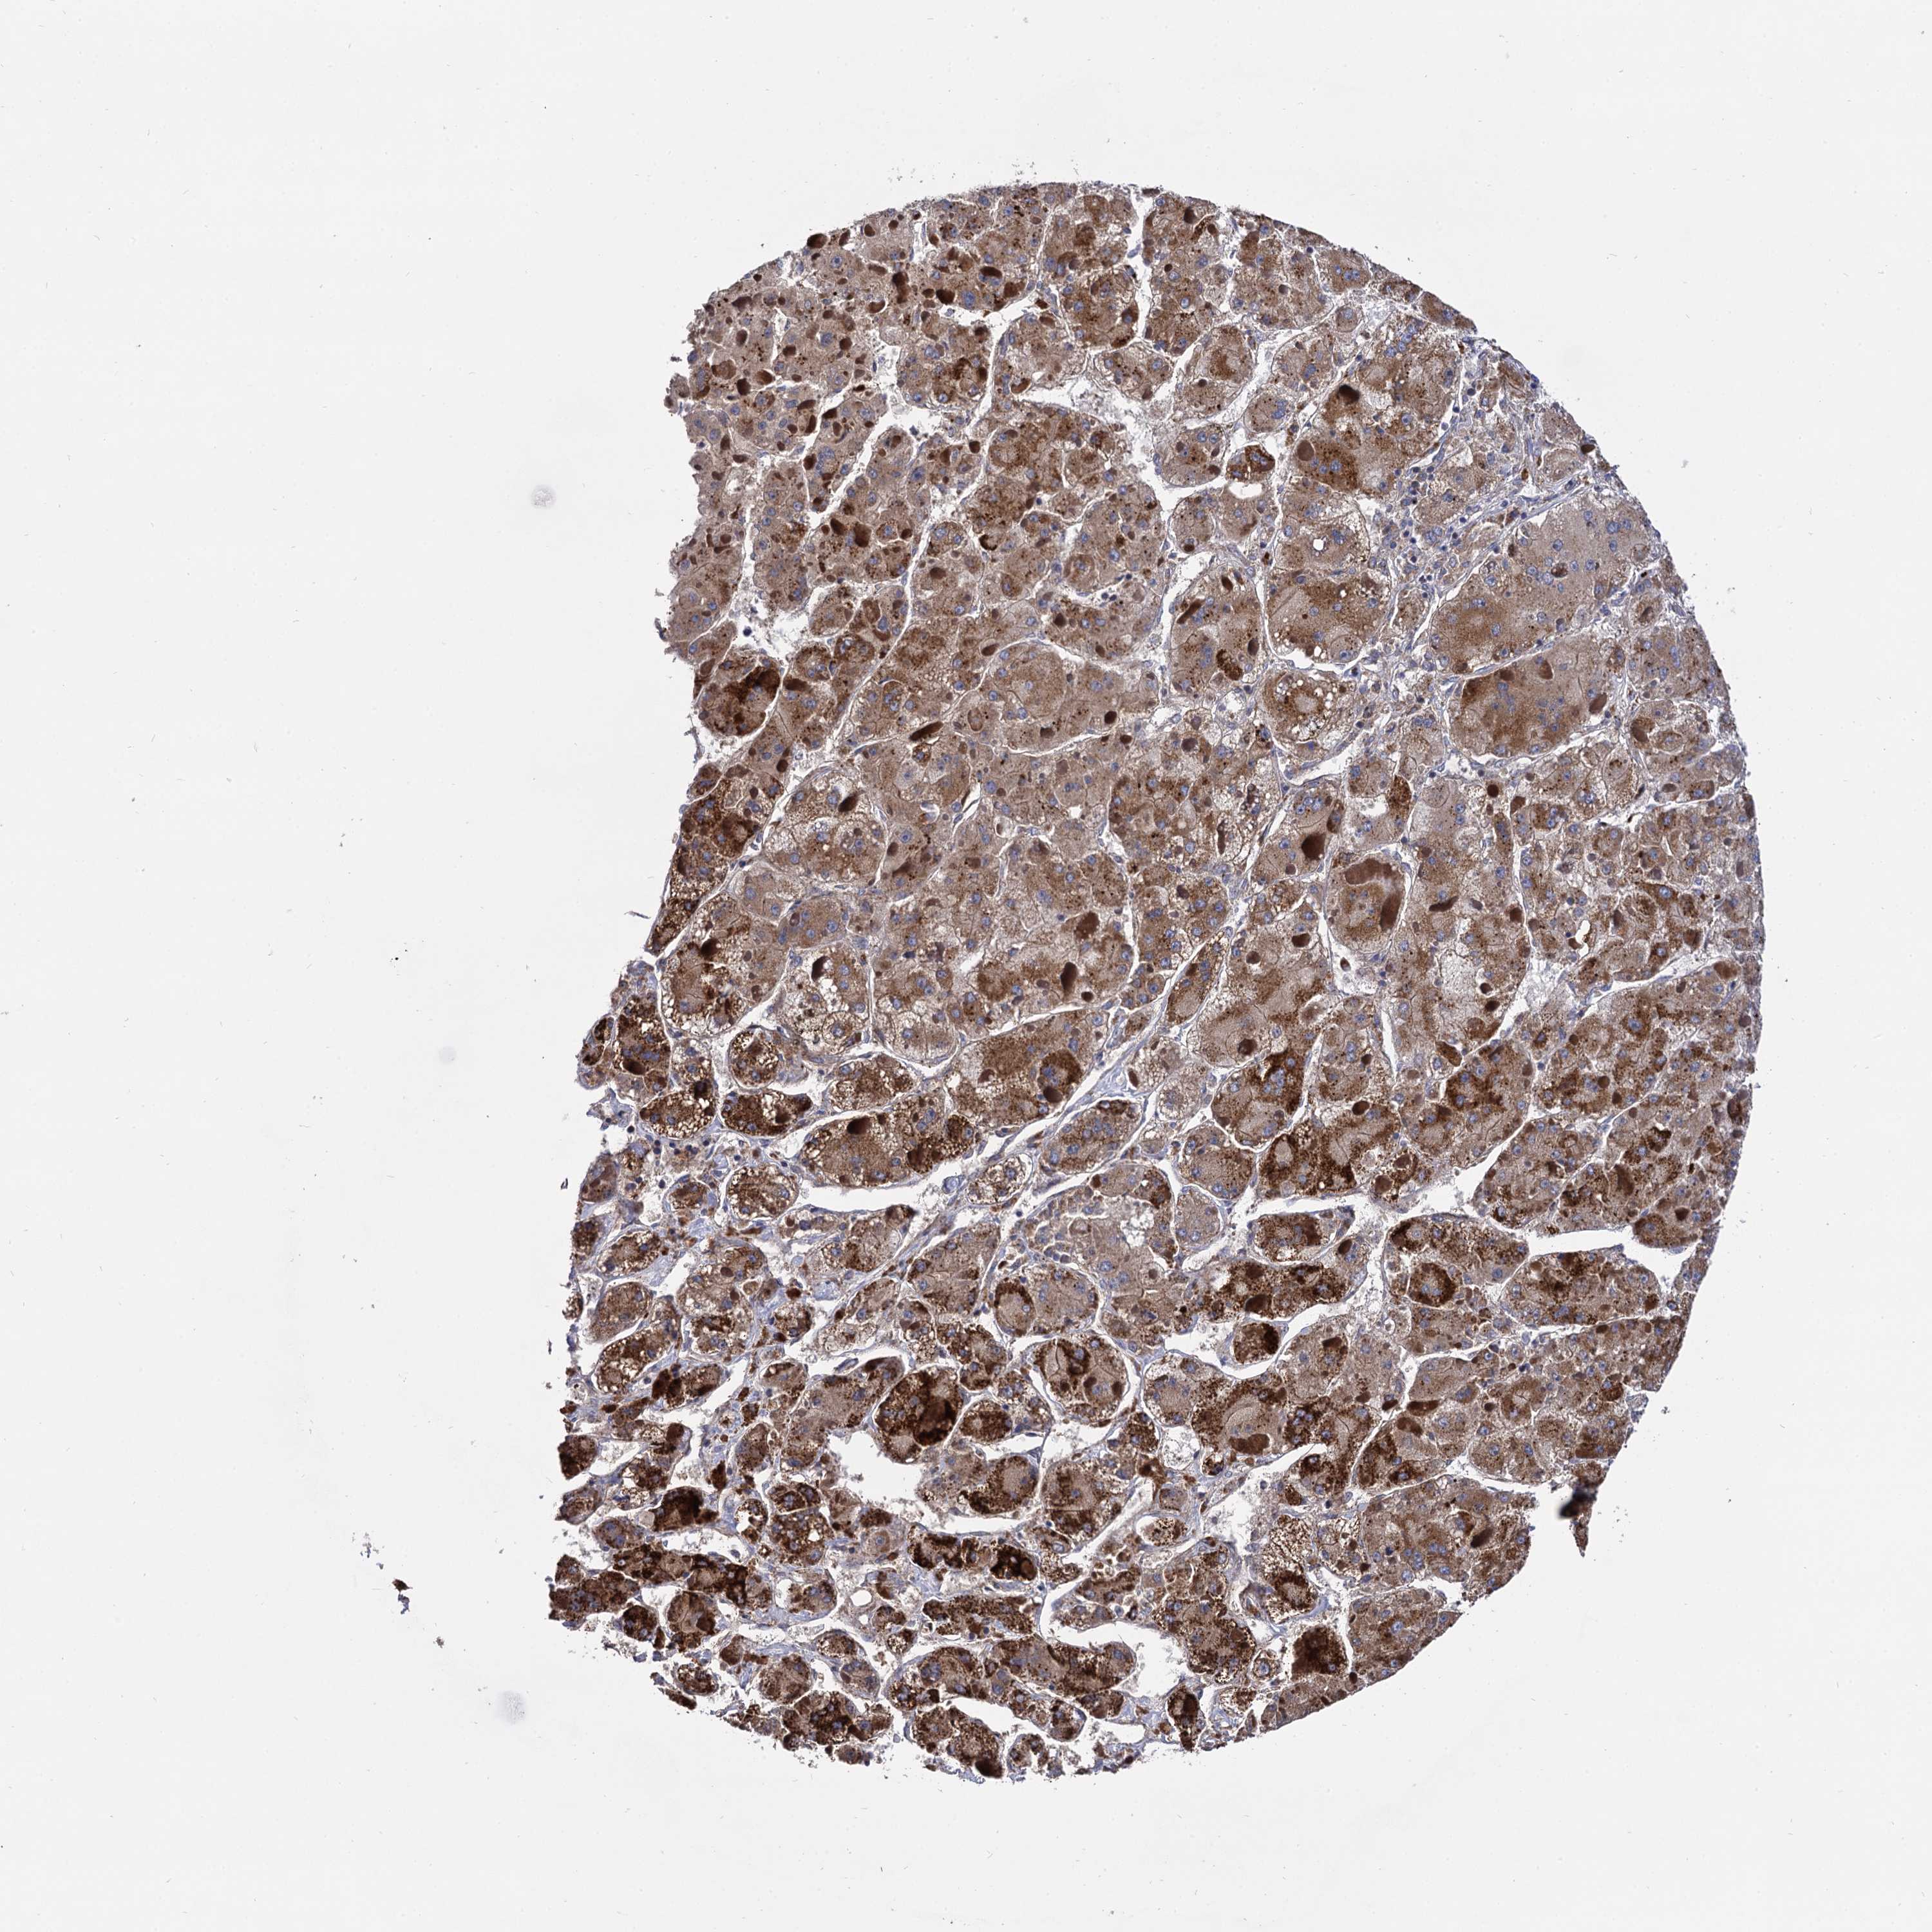

LIVER CANCER - Protein expressioni

A mouse-over function shows sample information and annotation data. Click on an image to view it in a full screen mode. Samples can be filtered based on level of antibody staining by selecting one or several of the following categories: high, medium, low and not detected. The assay and annotation is described here.

Note that samples used for immunohistochemistry by the Human Protein Atlas do not correspond to samples in the TCGA dataset.

Antibody stainingi

Antibody staining in the annotated cell types in the current human tissue is reported as not detected, low, medium, or high, based on conventional immunohistochemistry profiling in selected tissues. This score is based on the combination of the staining intensity and fraction of stained cells.

Each image is clickable and will lead to virtual microscopy that enables deeper exploration of all samples and also displays staining intensity scores, fraction scores and subcellular localization as well as patient and tissue information for each sample.

Antibody HPA040845

Staining

High

Medium

Low

Not detected

Intensity

Strong

Moderate

Weak

Negative

Quantity

>75%

75%-25%

<25%

None

Location

Nuclear

Cytoplasmic/membranous

Cytoplasmic/membranous,nuclear

Cholangiocarcinoma

Carcinoma, Hepatocellular, NOS